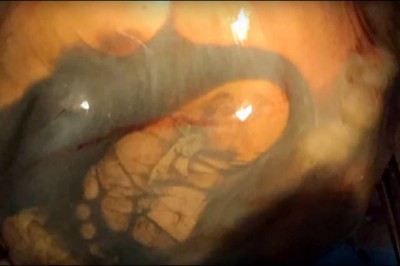

W 41 tygodniu ciąży przychodzi na USG! To co lekarz odkrywa podczas badań odbiera wszystkim mowę!

Niedawne narodziny ważącej 4.1 kilograma dziewczynki w regionie Altai na Syberii, stały się wydarzeniem które przejdzie do historii medycyny. Lekarze zgodnie twierdzą, że szansa na donoszenie ciąży pozamacicznej i urodzenie zdrowego dziecka, jest praktycz...